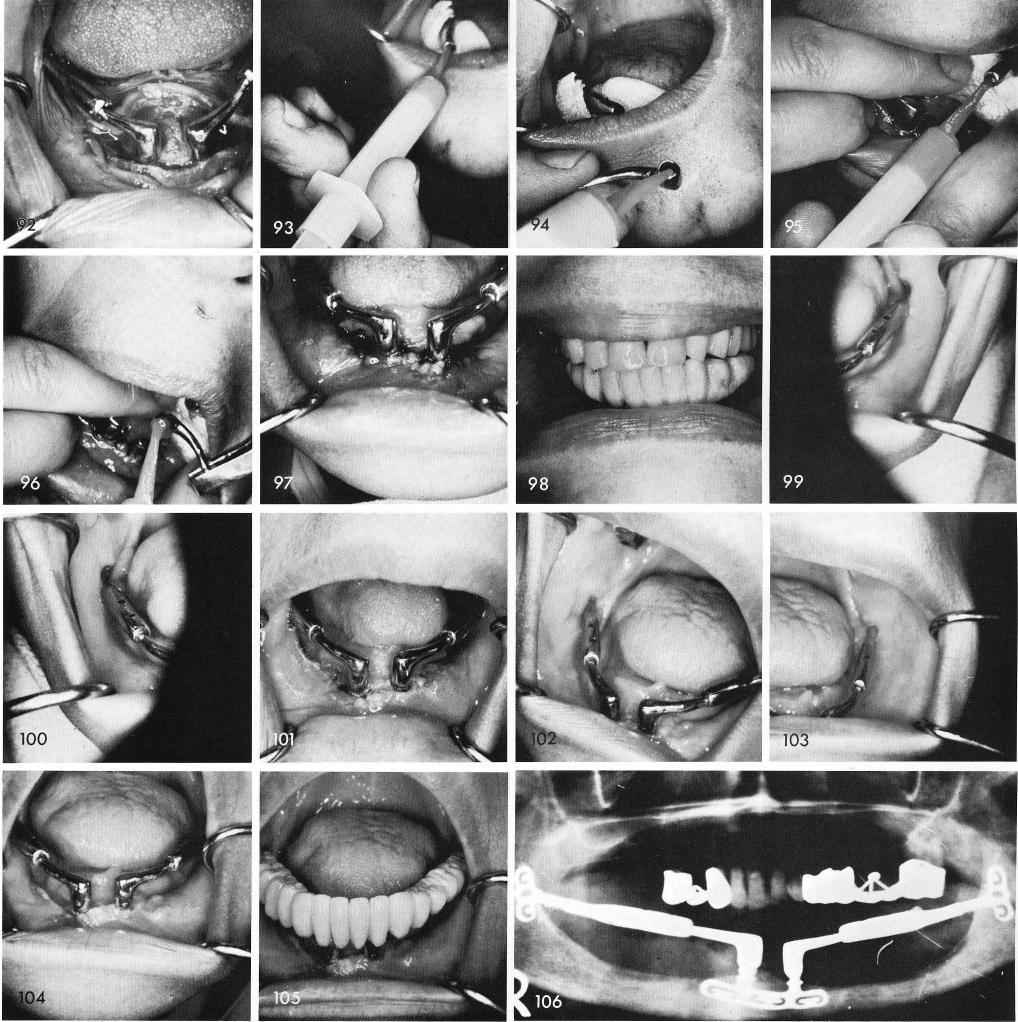

in be introduced, figs. 93, 94, 95, 96, 97. A temporary acrylic splint is cold cured and the bite is 1justed, fig. 98. The healed sites posteriorly, figs. 99, 100, and anteriorly the day that the sutures 2,re removed, fig. 101. Two weeks later, figs. 102, 103, 104, and the acrylic splint, fig. 105. The ray shows this case two & one half years post-operatively functioning against maxillary natural eth, fig. 106.

1 Acrylic splint cold cured over symphyseal ramus system